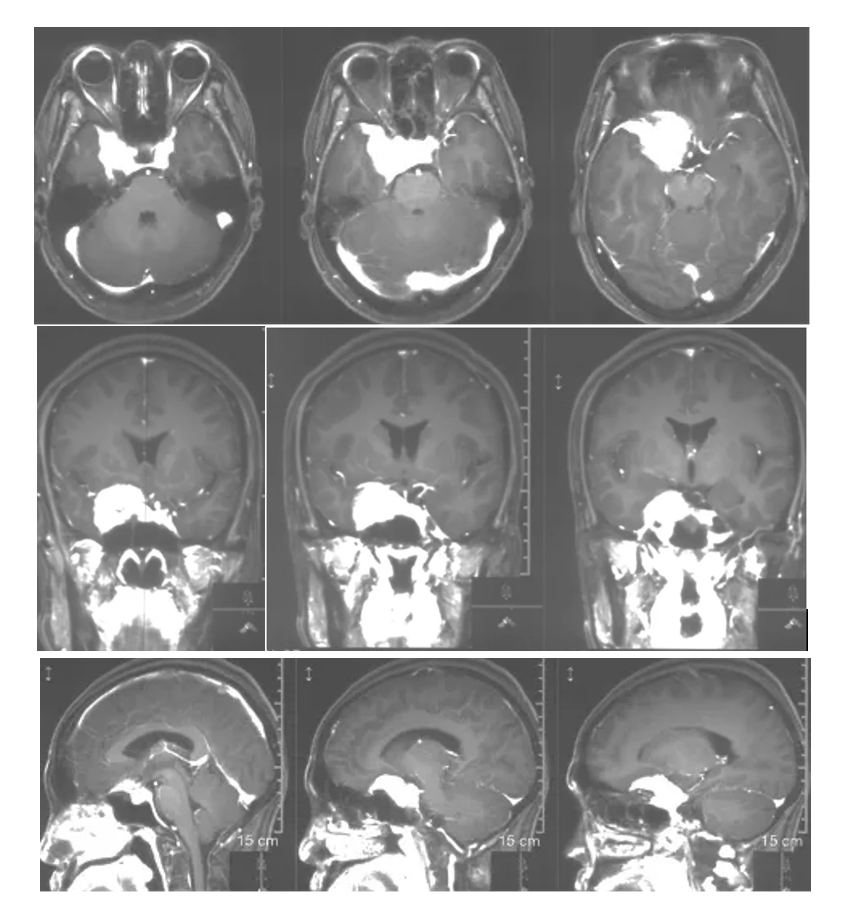

Cranial MRI enhanced

1. MRI T1 and T2 images showed a solid tumor in the medial region of the right sphenoid crest with long T1 and short T2 signals, and peritumoral edema was not obvious.

2. Enhanced axial, coronal and sagittal positions showed that the tumor strengthened uniformly with a broad base, mainly located in the medial part of the right sphenoid crest, the base of middle cranial fossa, the saddle diaphragm, encroaching on the cavernous sinus bilaterally, and the internal carotid artery, the middle cerebral artery and the anterior cerebral artery and their perforating blood vessels were encircled by the tumor.

CT bone window of the skull base

No significant enlargement of the right optic canal